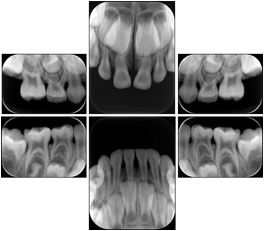

3. A dental provider wishes to capture a series of DICOM IO images for the patient’s dentition. The tooth morphology, teeth are divided into molars, premolars, canines and incisors, and a number of images for each jaw. The anatomic information was captured utilizing the triplet of schema. This standard code sequence is based on ISO 3950-2010, Dentistry - Designation system for teeth and areas of the oral cavity.

Every IO image should have anatomic information either through the primary or modifier sequence.

In most standard cases, images are oriented in structured layouts. These structured displays are useful to be shared between providers for reference purposes.

Table OO.1.1-1 shows structured display standard templates, where Viewset ID is based on the Japanese Society for Oral and Maxillofacial Radiology (JSOMR) classification provided by JIRA (Japan Medical Imaging and Radiological Systems Industries Association, www.jira-net.or.jp). Expected or typical teeth to be imaged location, region and designation codes are based on ISO 3950-2010, Dentistry - Designation system for teeth and areas of the oral cavity. For all the hanging protocols listed in OO.1.1-1, the value to use for Hanging Protocol Creator (0072,0008) is "JSOMR" and the value to use for Hanging Protocol Name (0072,0002) does not include "JSOMR" (e.g., "DL-S001A", not "JSOMR DL-S001A").